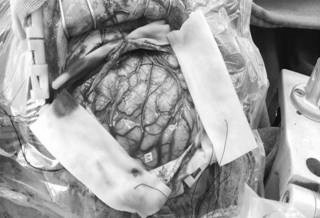

微侵袭神经外科的吴杰主任考虑小月的癫痫灶为右额中央区的结节性硬化病变。几日后,吴杰主任为其实施了“右额中央区癫痫灶切除术”,术中经导航确认病灶组织;皮层电极检查局部有少量尖波发放,电刺激术区均未有运动反应,医生在显微镜下切除病变。

术中